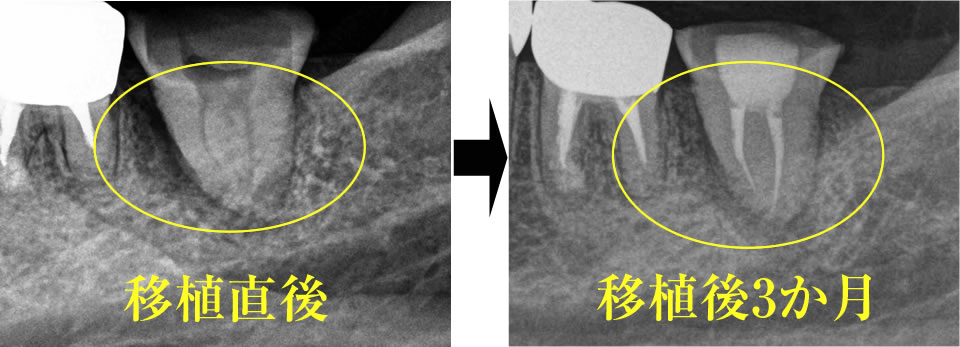

移植後3か月のレントゲン写真。移植直後のレントゲン写真と比べてもらうと、歯の周りが白くなっているのがわかると思います。これは移植歯の周りに骨が出来ていることを表します。